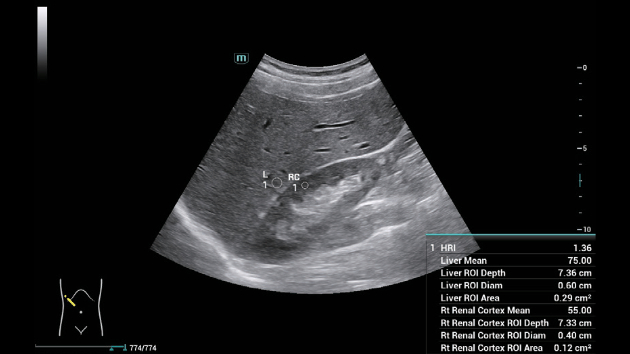

Smart HRI: автоматизированная оценка стеатоза печени с высокой точностью

Smart HRI (Hepato-Renal Index) — это интеллектуальный протокол, автоматически определяющий гепаторенальный индекс для оценки стеатоза печени. Технология анализирует соотношение эхогенности тканей печени и коркового слоя почек, используя алгоритмы обработки радиочастотных данных и сравнения яркости изображений. В аппаратах серии Consona, таких как N6 и N9, Smart HRI интегрирован с платформой ZST+, что обеспечивает высокую точность измерений за счет улучшенного разрешения и подавления шумов. Это позволяет системе автоматически выделять зоны интереса и минимизировать влияние субъективных факторов на диагностику.

Smart HRI: автоматизированная оценка стеатоза печени с высокой точностью

Smart HRI (Hepato-Renal Index) — это интеллектуальный протокол, автоматически определяющий гепаторенальный индекс для оценки стеатоза печени. Технология анализирует соотношение эхогенности тканей печени и коркового слоя почек, используя алгоритмы обработки радиочастотных данных и сравнения яркости изображений. В аппаратах серии Consona, таких как N6 и N9, Smart HRI интегрирован с платформой ZST+, что обеспечивает высокую точность измерений за счет улучшенного разрешения и подавления шумов. Это позволяет системе автоматически выделять зоны интереса и минимизировать влияние субъективных факторов на диагностику.